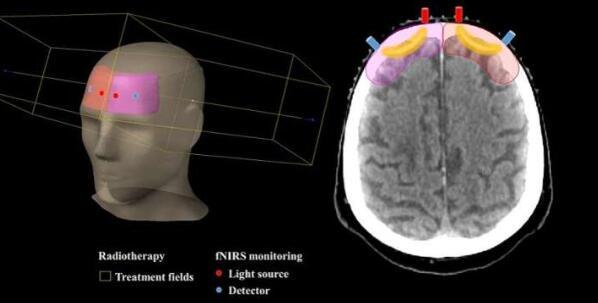

他们的方法涉及使用功能性近红外光谱(fNIRS)设备,该设备使用红外光来测量大脑中血红蛋白浓度的变化 - 组织氧合水平的指标。这种非侵入性技术通常用于研究大脑活动对不同刺激和认知任务的反应。然而,在这种情况下,研究人员用它来测量患者接受全脑放射治疗时大脑中血红蛋白浓度的变化,其中直线加速器用于向患者的大脑提供目标剂量的辐射。

Myllylä说:“使用多波长fNIRS的光纤装置被构建出来,并与医用直线加速器相结合,以测量脑部放射治疗期间的脑组织氧合变化,其中辐射剂量仅限于大脑区域以避免照射眼睛。

放射治疗会改变患者组织中的血液循环,并且由于血红蛋白水平是血容量变化的有用指标,因此使用fNIRS可以深入了解放射治疗对组织血液循环的影响。利用他们的技术,研究人员成功地测量了10名患者的组织氧合水平,并观察到患者在治疗期间接受多次照射时水平的瞬时变化。